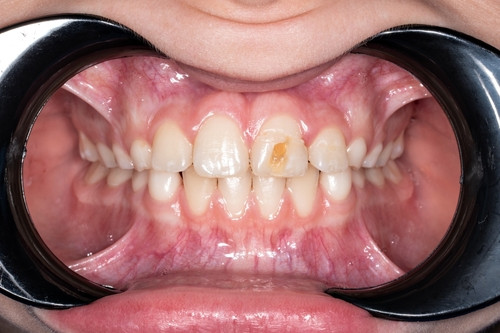

Пятнистая форма — сопровождается образованием симметричных пятен на поверхности эмали. Они имеют желтоватый или белый оттенок. Могут быть одиночными или множественными, в зависимости от тяжести ситуации. Обычно не доставляют существенного дискомфорта, хотя и выглядят неэстетично. Дефект обычно поверхностный, эмаль частично сохранена, как и ее функции.

- изменение цвета зубов: с белого на желтый или же желтовато-коричневый, в зависимости от ситуации, что выглядит неэстетично;

- образование четко выраженных визуальных дефектов: неправильной или правильной формы, часто с четкой границей (например, полоски на передней поверхности резцов);